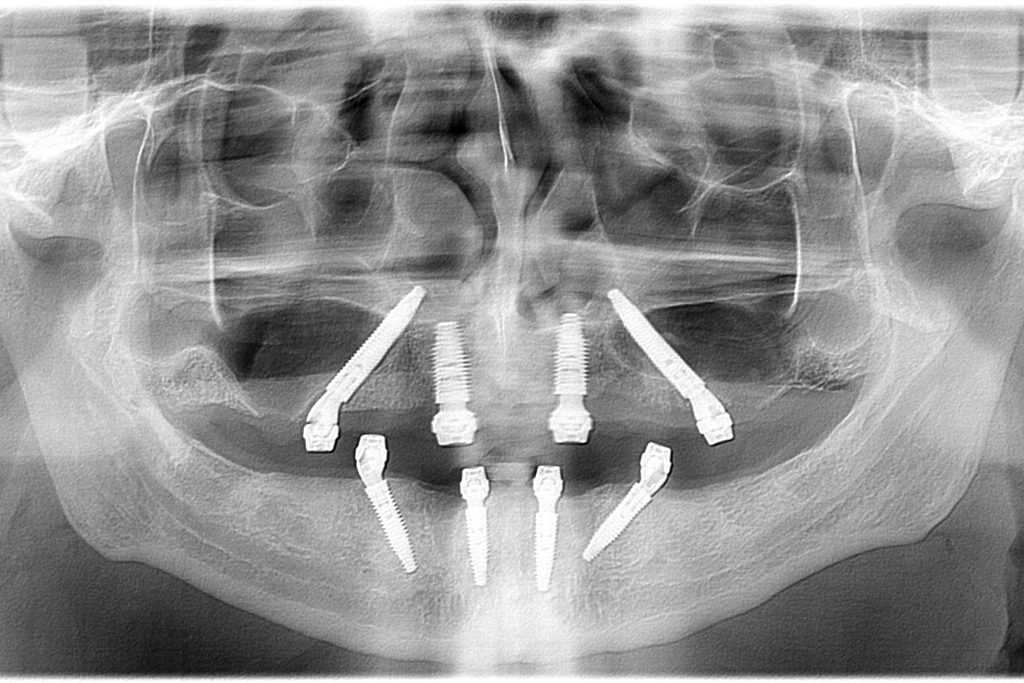

CBCT Mandibula

CBCT analysis of both jaws show available bone for fixed implant born dental restoration

Double All-on-4 surgery Belgrade

Control Panoramic X ray image right after surgery showing Neodent GM Helix implants